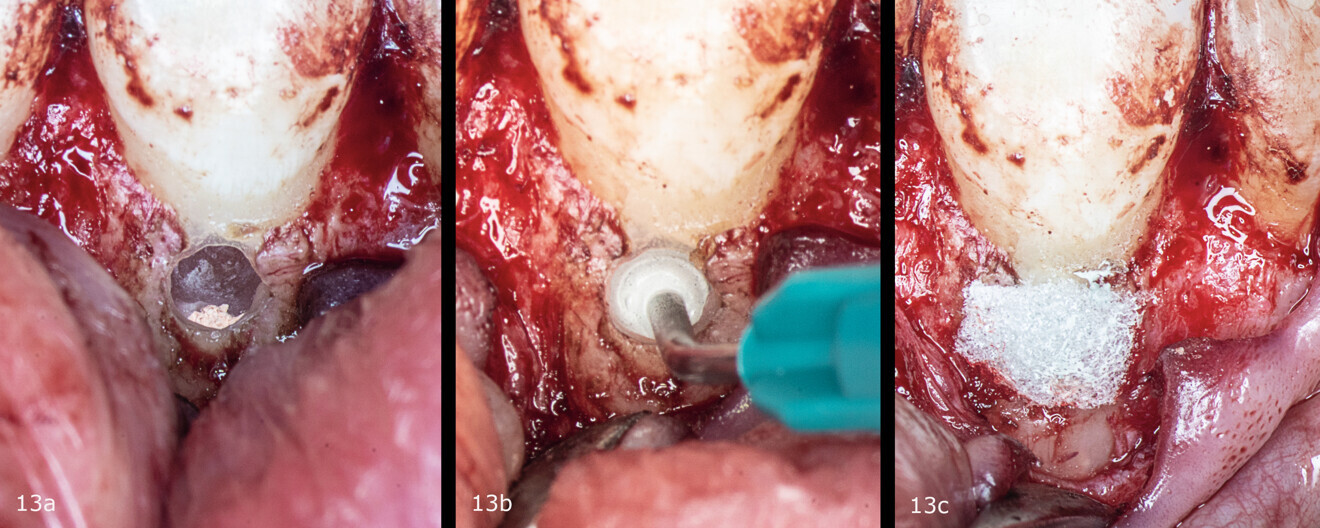

Figs. 13a–c: Application of the biomaterial in the resorption cavity and placement of collagen sponge on top.

The obturation of choice was warm vertical compaction of gutta-percha and sealing with the AH Plus sealer (Dentsply Sirona). The resorption cavity was filled with a fast-setting mineral trioxide aggregate (Harvard Dental), the coronal part of the root canal was filled with warm gutta-percha and collagen sponge was placed (Figs. 12a & b; Figs. 13a & b). The flap was repositioned and sutured, and the tooth was restored with the GRADIA composite resin (GC; Figs. 14a & b, Fig. 15).